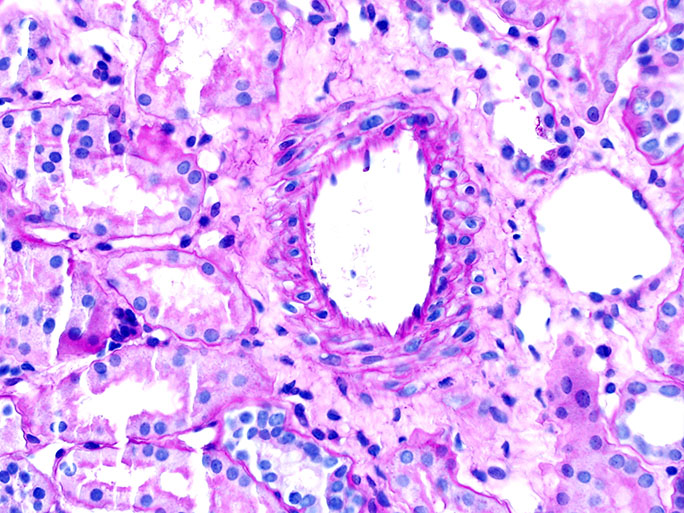

2. Periodic Acid Schiff or PAS: stains carbohydrates and carbohydrate rich macromolecules including collagen a deep red or magenta color

A kidney pathology tip to identify a hypercellular glomerulus: try the chocolate chip cookie analogy (i.e. more chips = more cells)